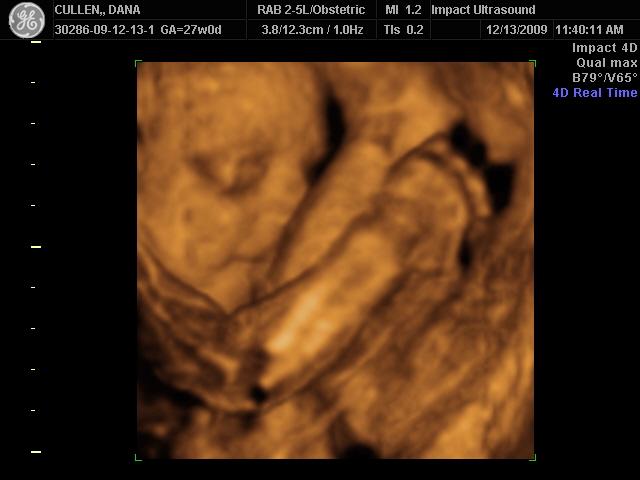

Re: Girls who had 3D/4D sonos, please post...

I went to Impact at 27 weeks. Here's DD

Image Attachment(s):